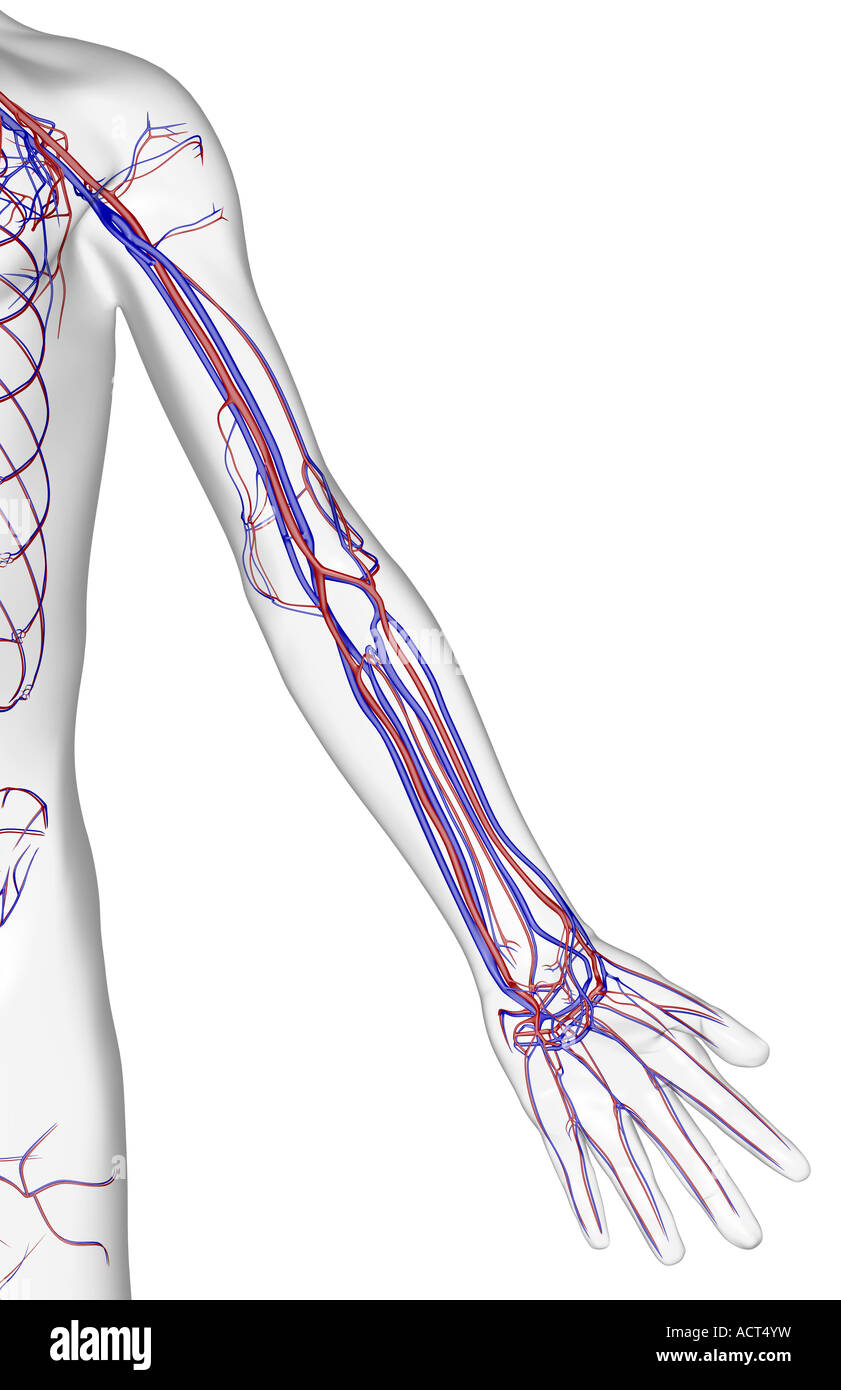

The blood supply of the upper limb Stock Photohttps://www.alamy.com/image-license-details/?v=1https://www.alamy.com/stock-photo-the-blood-supply-of-the-upper-limb-13223052.html

The blood supply of the upper limb Stock Photohttps://www.alamy.com/image-license-details/?v=1https://www.alamy.com/stock-photo-the-blood-supply-of-the-upper-limb-13223052.htmlRFACT4YW–The blood supply of the upper limb